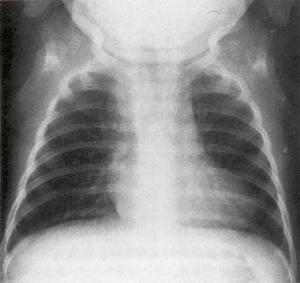

(X線檢查) 心臟大小正常或稍增大,心尖圓鈍上翹,肺動脈段凹陷,構成“靴狀”心影,肺門血管影縮小,兩側肺紋理減少,透亮度增加。側支循環豐富者兩肺野呈現網狀肺 (心電圖) 電軸右偏,右心室肥大,狹窄嚴重者往往出現心肌勞損,亦可見右心房肥大。

(2)胸部X線檢查左心腰凹陷,心尖圓鈍上翹,主動脈結突出,呈“靴狀心”。肺野血管纖細。輕型病人肺動脈凹陷不明顯,肺野血管輕度減少或正常。

1月女孩,法洛四聯症胸部X線象 治療方法